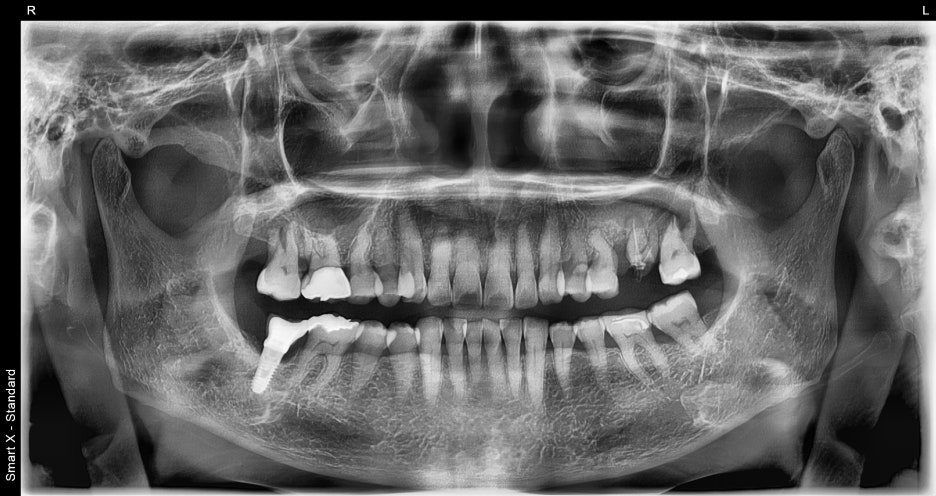

처음 내원 한 당시

서울오브치과병원에서는 모든 임플란트 치료 전에

3D CT를 촬영합니다.

이번 케이스에서는

#26, #27 주변의 심한 골소실

상악동이 매우 낮아진 상태

치근과 잇몸 사이의 염증

이 확인되었습니다.

파노라마 엑스레이와 구강내 사진을 통해 확인한 결과,

왼쪽 위 두 개의 어금니가 파절 및 결손 상태

주변 치조골은 비교적 건강하여 뼈이식이

최소화된 상태에서도 임플란트 식립 가능

이라는 진단을 내렸습니다.